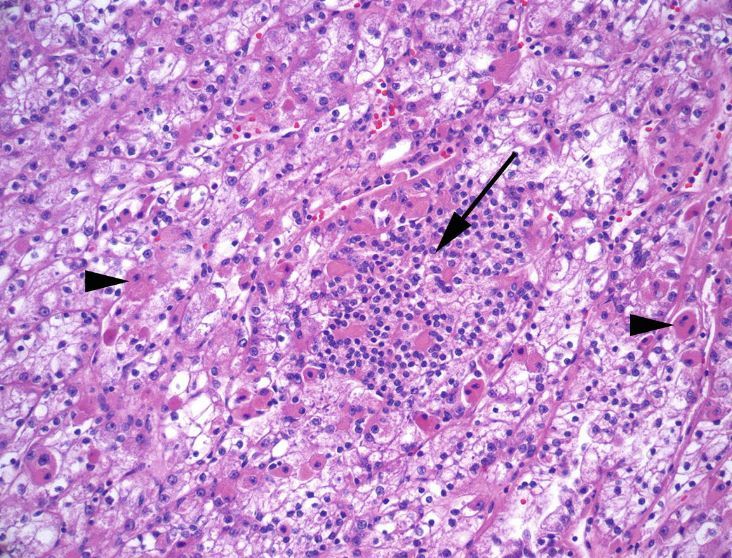

t(6;11) renal cell carcinoma

Unique in its dual cell population: Nests of large clear or granular pink cells interspersed with aggregates of small compact cells that may be mistaken for lymphocytes at low power.

Oddly, this carcinoma stains positive for HMB-45, Melan-A, but not keratin or S100, which can lead to confusion for an epithelioid myelolipoma.

A member of the MiT family translocation RCCs.